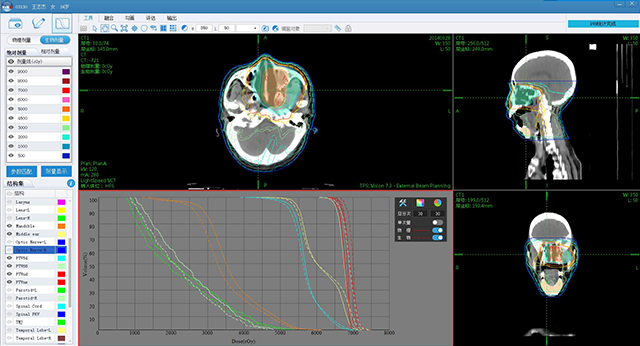

ж”ҫз–—еӯҰ科е»әи®ҫ

иӮҝзҳӨж”ҫз–—дҝЎжҒҜеҢ–дә§е“Ғ

е®үиҜәдә‘жҷәиҝңзЁӢж”ҫз–—еҚҸдҪңе№іеҸ°